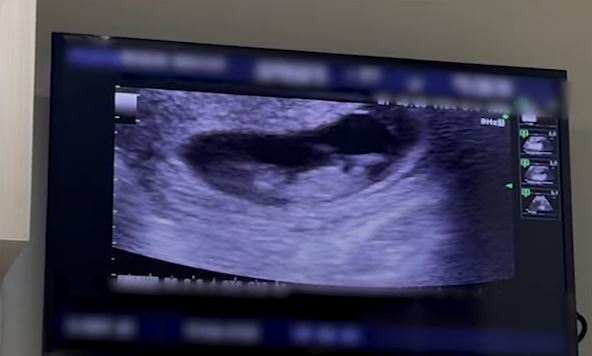

โดยเผยว่าตอนนี้ตั้งท้องกับแฟนหนุ่มชาวฝรั่งเศสได้ 3 เดือนแล้ว ซึ่งก่อนหน้านี้

แบบธรรมชาติ ก็เลยเก็บไข่ได้ 7 วัน แล้วก็ให้คุณหมอดูวัน ตอนนี้แฮปปี้มาก พร้อมมีน้องแล้ว